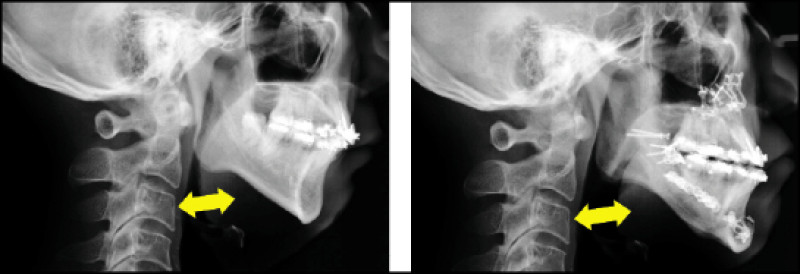

正顎手術 成功改善阻塞型睡眠呼吸中止症